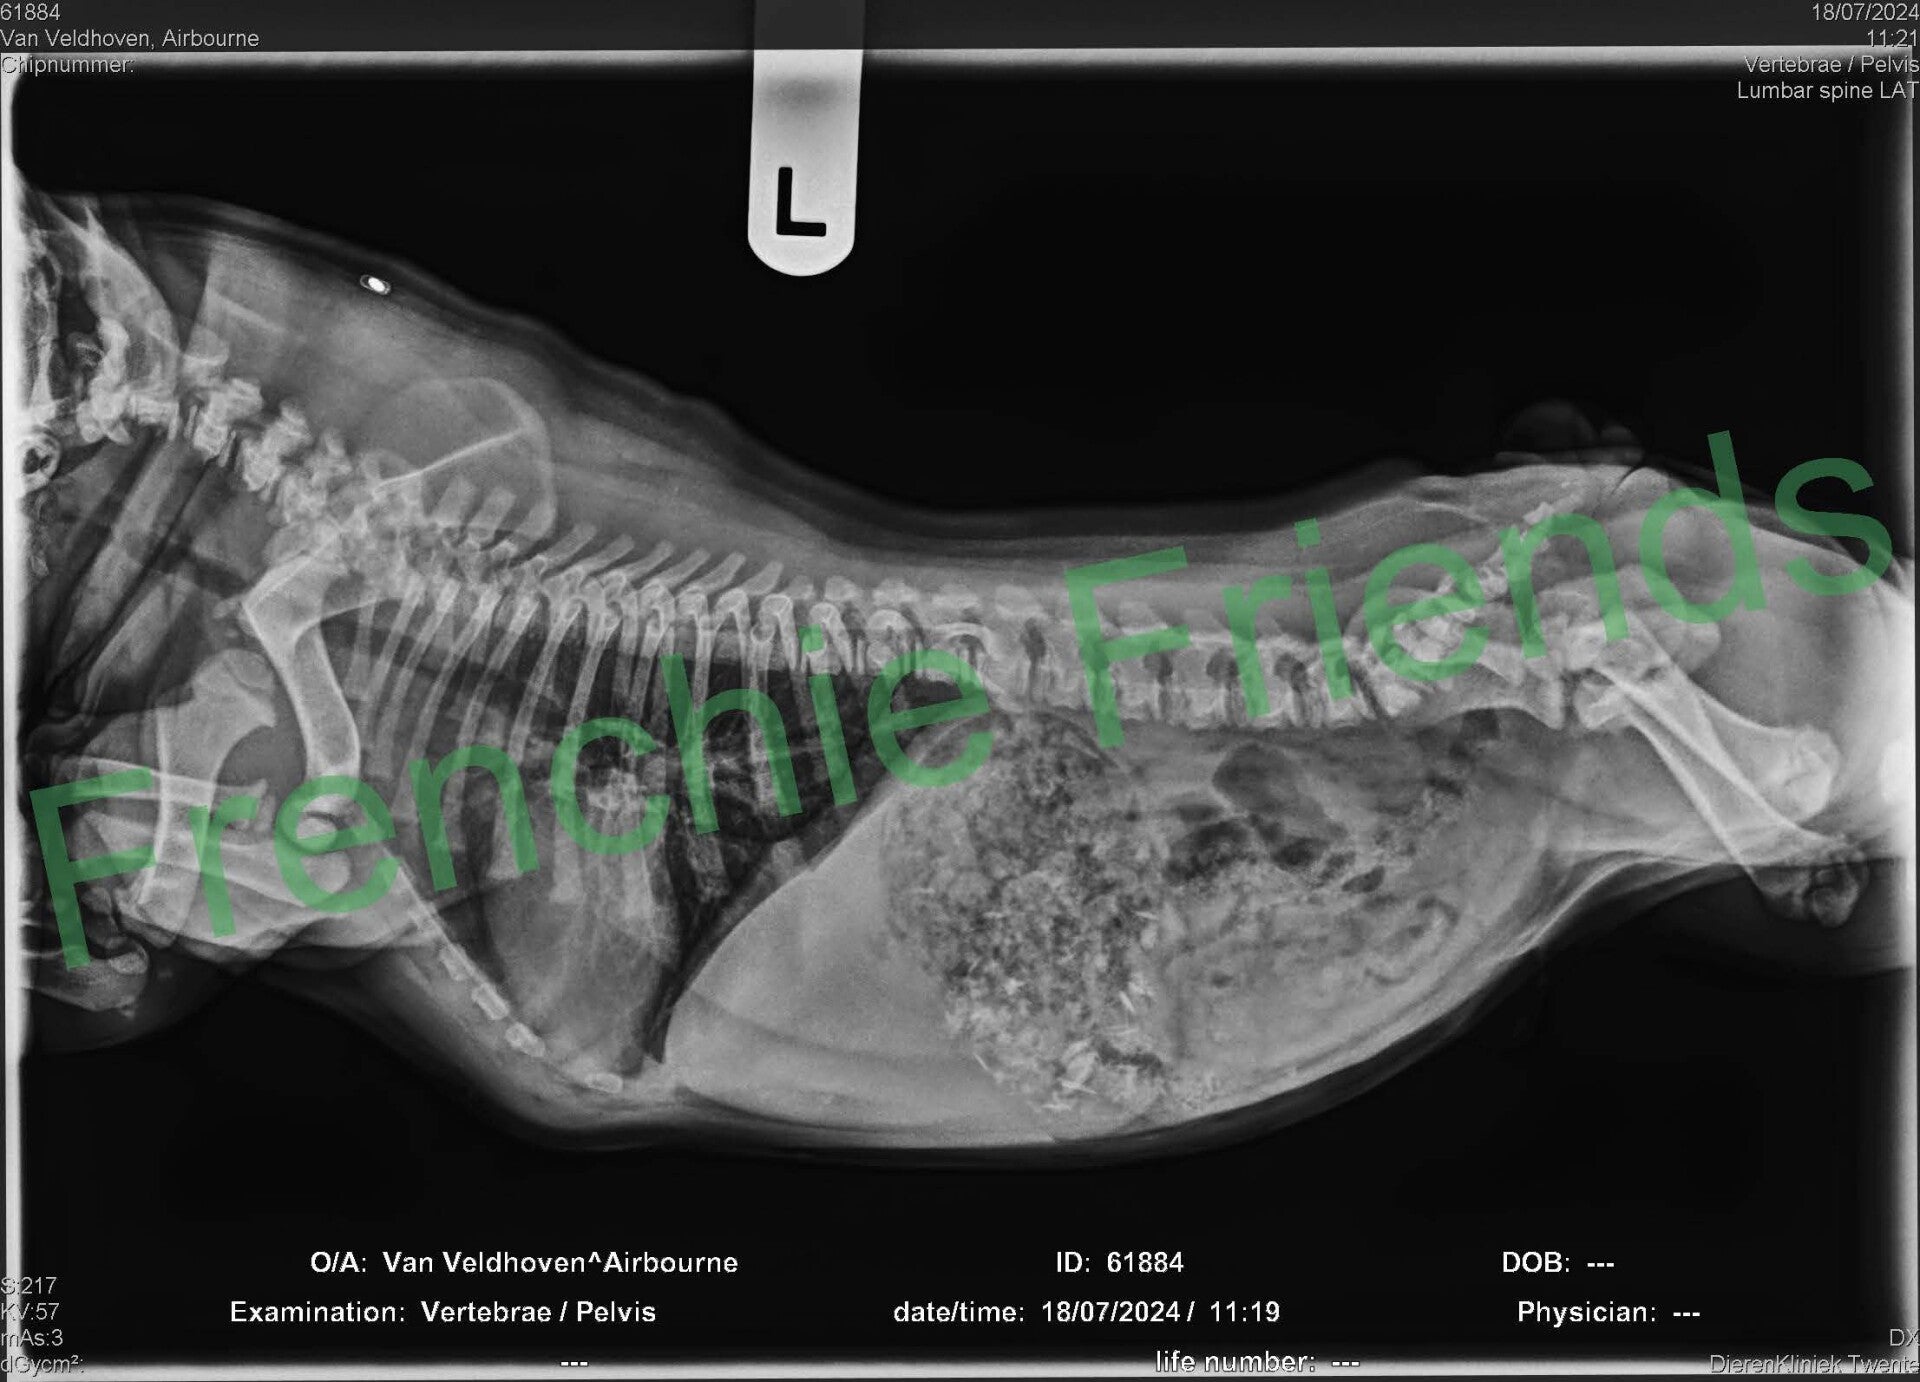

Op de röntgenfoto hadden we al gezien dat er 7 pupjes verwacht werden en alsof ze het al jaren zo deed perste Indy zonder problemen het ene na het andere pupje naar buiten. Bij nummer 5 werd het even spannend, maar mede dankzij mijn hulplijn met Esther, is ook dit pupje uiteindelijk goed en gezond ter wereld gekomen.

Met nummer 5 had Indy beduidend meer moeite. Het duurde even voor hij kwam en hij had wat opstartproblemen. Om 20.45 was hij er, een flinke lichte fawn reu van 269 gram; Airbourne (Nu Tommy). Tommy woont bij Tony en zijn gezin in Lopik. Een pittig mannetje, mag altijd mee naar het werk!